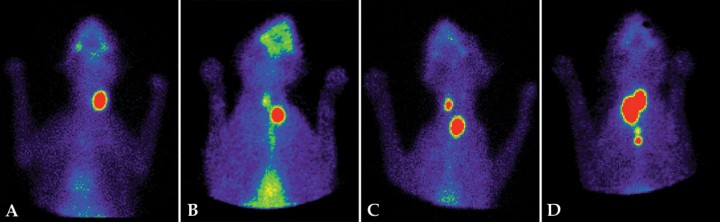

Aproximadamente un 30 % de los gatos hipertiroideos presentan un aumento de tamaño y una mayor captación del radiofármaco en un solo lóbulo tiroideo (patrón unilateral) (Fig. 2A).[ Xifra MP, Peterson ME. Hipertiroidismo felino. En: Pérez MD, Arenas C, Melian C (eds): Manual de Endocrinología en Pequeños Animales. 2ª ed. Barcelona, España. Multimédica; 2018:143-192. , Peterson ME, Broome MR. Thyroid scintigraphy findings in 2096 cats with hyperthyroidism. Vet Radiol Ultrasound. 2015; 56(1):84-95. [PubMed] ] El lóbulo contralateral normal no será visible al tener su funcionalidad disminuida y no captar pertecnetato, ya que el lóbulo hiperfuncional suprime la secreción de tirotropina (TSH).[ Xifra MP, Peterson ME. Hipertiroidismo felino. En: Pérez MD, Arenas C, Melian C (eds): Manual de Endocrinología en Pequeños Animales. 2ª ed. Barcelona, España. Multimédica; 2018:143-192. ] Si el lóbulo contralateral presenta captación del radiofármaco, aunque la ratio T/S no esté aumentada, se considera que su tejido es hiperfuncional y, por lo tanto, se clasifica como patrón bilateral (Fig. 2B).[ Xifra MP, Peterson ME. Hipertiroidismo felino. En: Pérez MD, Arenas C, Melian C (eds): Manual de Endocrinología en Pequeños Animales. 2ª ed. Barcelona, España. Multimédica; 2018:143-192. , Peterson ME, Broome MR. Thyroid scintigraphy findings in 2096 cats with hyperthyroidism. Vet Radiol Ultrasound. 2015; 56(1):84-95. [PubMed] ]

<p>Gammagrafías tiroideas con diferentes patrones de lesión en gatos. (<strong>A</strong>) Gato hipertiroideo, patrón unilateral. Aumento de captación de <sup>99m</sup>Tc (ratio T/S: 4,8) en el lóbulo tiroideo izquierdo. Lóbulo derecho suprimido y no visible. (<strong>B</strong>) Gato hipertiroideo, patrón bilateral. Aumento de captación (ratio T/S: 2,7) en el lóbulo tiroideo izquierdo. El lóbulo derecho es visible, y aunque su captación tenga una ratio T/S<1,5 (=1,06), se considera hiperfuncional. (<strong>C</strong>) Gato hipertiroideo, patrón bilateral asimétrico. Aumento de captación (ratio T/S: 6,35) en ambos lóbulos. El lóbulo tiroideo izquierdo, de mayor tamaño, aparece desplazado a la entrada de la cavidad torácica. (<strong>D</strong>) Gato hipertiroideo, patrón multifocal con tejido ectópico. Aumento de captación (ratio T/S: 14,4) en los dos lóbulos tiroideos y en tejido tiroideo ectópico mediastínico.</p>

Gammagrafías tiroideas con diferentes patrones de lesión en gatos. (A) Gato hipertiroideo, patrón unilateral. Aumento de captación de 99mTc (ratio T/S: 4,8) en el lóbulo tiroideo izquierdo. Lóbulo derecho suprimido y no visible. (B) Gato hipertiroideo, patrón bilateral. Aumento de captación (ratio T/S: 2,7) en el lóbulo tiroideo izquierdo. El lóbulo derecho es visible, y aunque su captación tenga una ratio T/S<1,5 (=1,06), se considera hiperfuncional. (C) Gato hipertiroideo, patrón bilateral asimétrico. Aumento de captación (ratio T/S: 6,35) en ambos lóbulos. El lóbulo tiroideo izquierdo, de mayor tamaño, aparece desplazado a la entrada de la cavidad torácica. (D) Gato hipertiroideo, patrón multifocal con tejido ectópico. Aumento de captación (ratio T/S: 14,4) en los dos lóbulos tiroideos y en tejido tiroideo ectópico mediastínico.

El 70 % de los gatos hipertiroideos presentan un patrón bilateral con afectación de ambos lóbulos (Fig. 2C).[ Xifra MP, Peterson ME. Hipertiroidismo felino. En: Pérez MD, Arenas C, Melian C (eds): Manual de Endocrinología en Pequeños Animales. 2ª ed. Barcelona, España. Multimédica; 2018:143-192. , Peterson ME, Broome MR. Thyroid scintigraphy findings in 2096 cats with hyperthyroidism. Vet Radiol Ultrasound. 2015; 56(1):84-95. [PubMed] ] En estos casos el aumento de tamaño y captación puede ser simétrico o asimétrico.

En un pequeño número de gatos, el hipertiroidismo puede estar producido por lesiones multifocales (más de dos áreas de captación del radionucleótido).[ Xifra MP, Peterson ME. Hipertiroidismo felino. En: Pérez MD, Arenas C, Melian C (eds): Manual de Endocrinología en Pequeños Animales. 2ª ed. Barcelona, España. Multimédica; 2018:143-192. , Peterson ME, Broome MR. Thyroid scintigraphy findings in 2096 cats with hyperthyroidism. Vet Radiol Ultrasound. 2015; 56(1):84-95. [PubMed] ] Como la gammagrafía tiroidea evidencia todo el tejido tiroideo existente, es muy útil para detectar lesiones en cualquier localización. Un pequeño porcentaje de gatos (<4 %) presenta tejido tiroideo ectópico, localizado desde el área sublingual hasta el mediastino craneal, que puede aparecer hiperfuncional en casos de hipertiroidismo (Fig. 2D). También permite visualizar lóbulos tiroideos hiperfuncionales desplazados a la cavidad torácica, ya que la glándula tiroidea está poco adherida a los tejidos adyacentes y, al hipertrofiarse, aumenta de peso y puede introducirse en la cavidad torácica.[ Xifra MP, Peterson ME. Hipertiroidismo felino. En: Pérez MD, Arenas C, Melian C (eds): Manual de Endocrinología en Pequeños Animales. 2ª ed. Barcelona, España. Multimédica; 2018:143-192. , Peterson ME, Broome MR. Thyroid scintigraphy findings in 2096 cats with hyperthyroidism. Vet Radiol Ultrasound. 2015; 56(1):84-95. [PubMed] ]